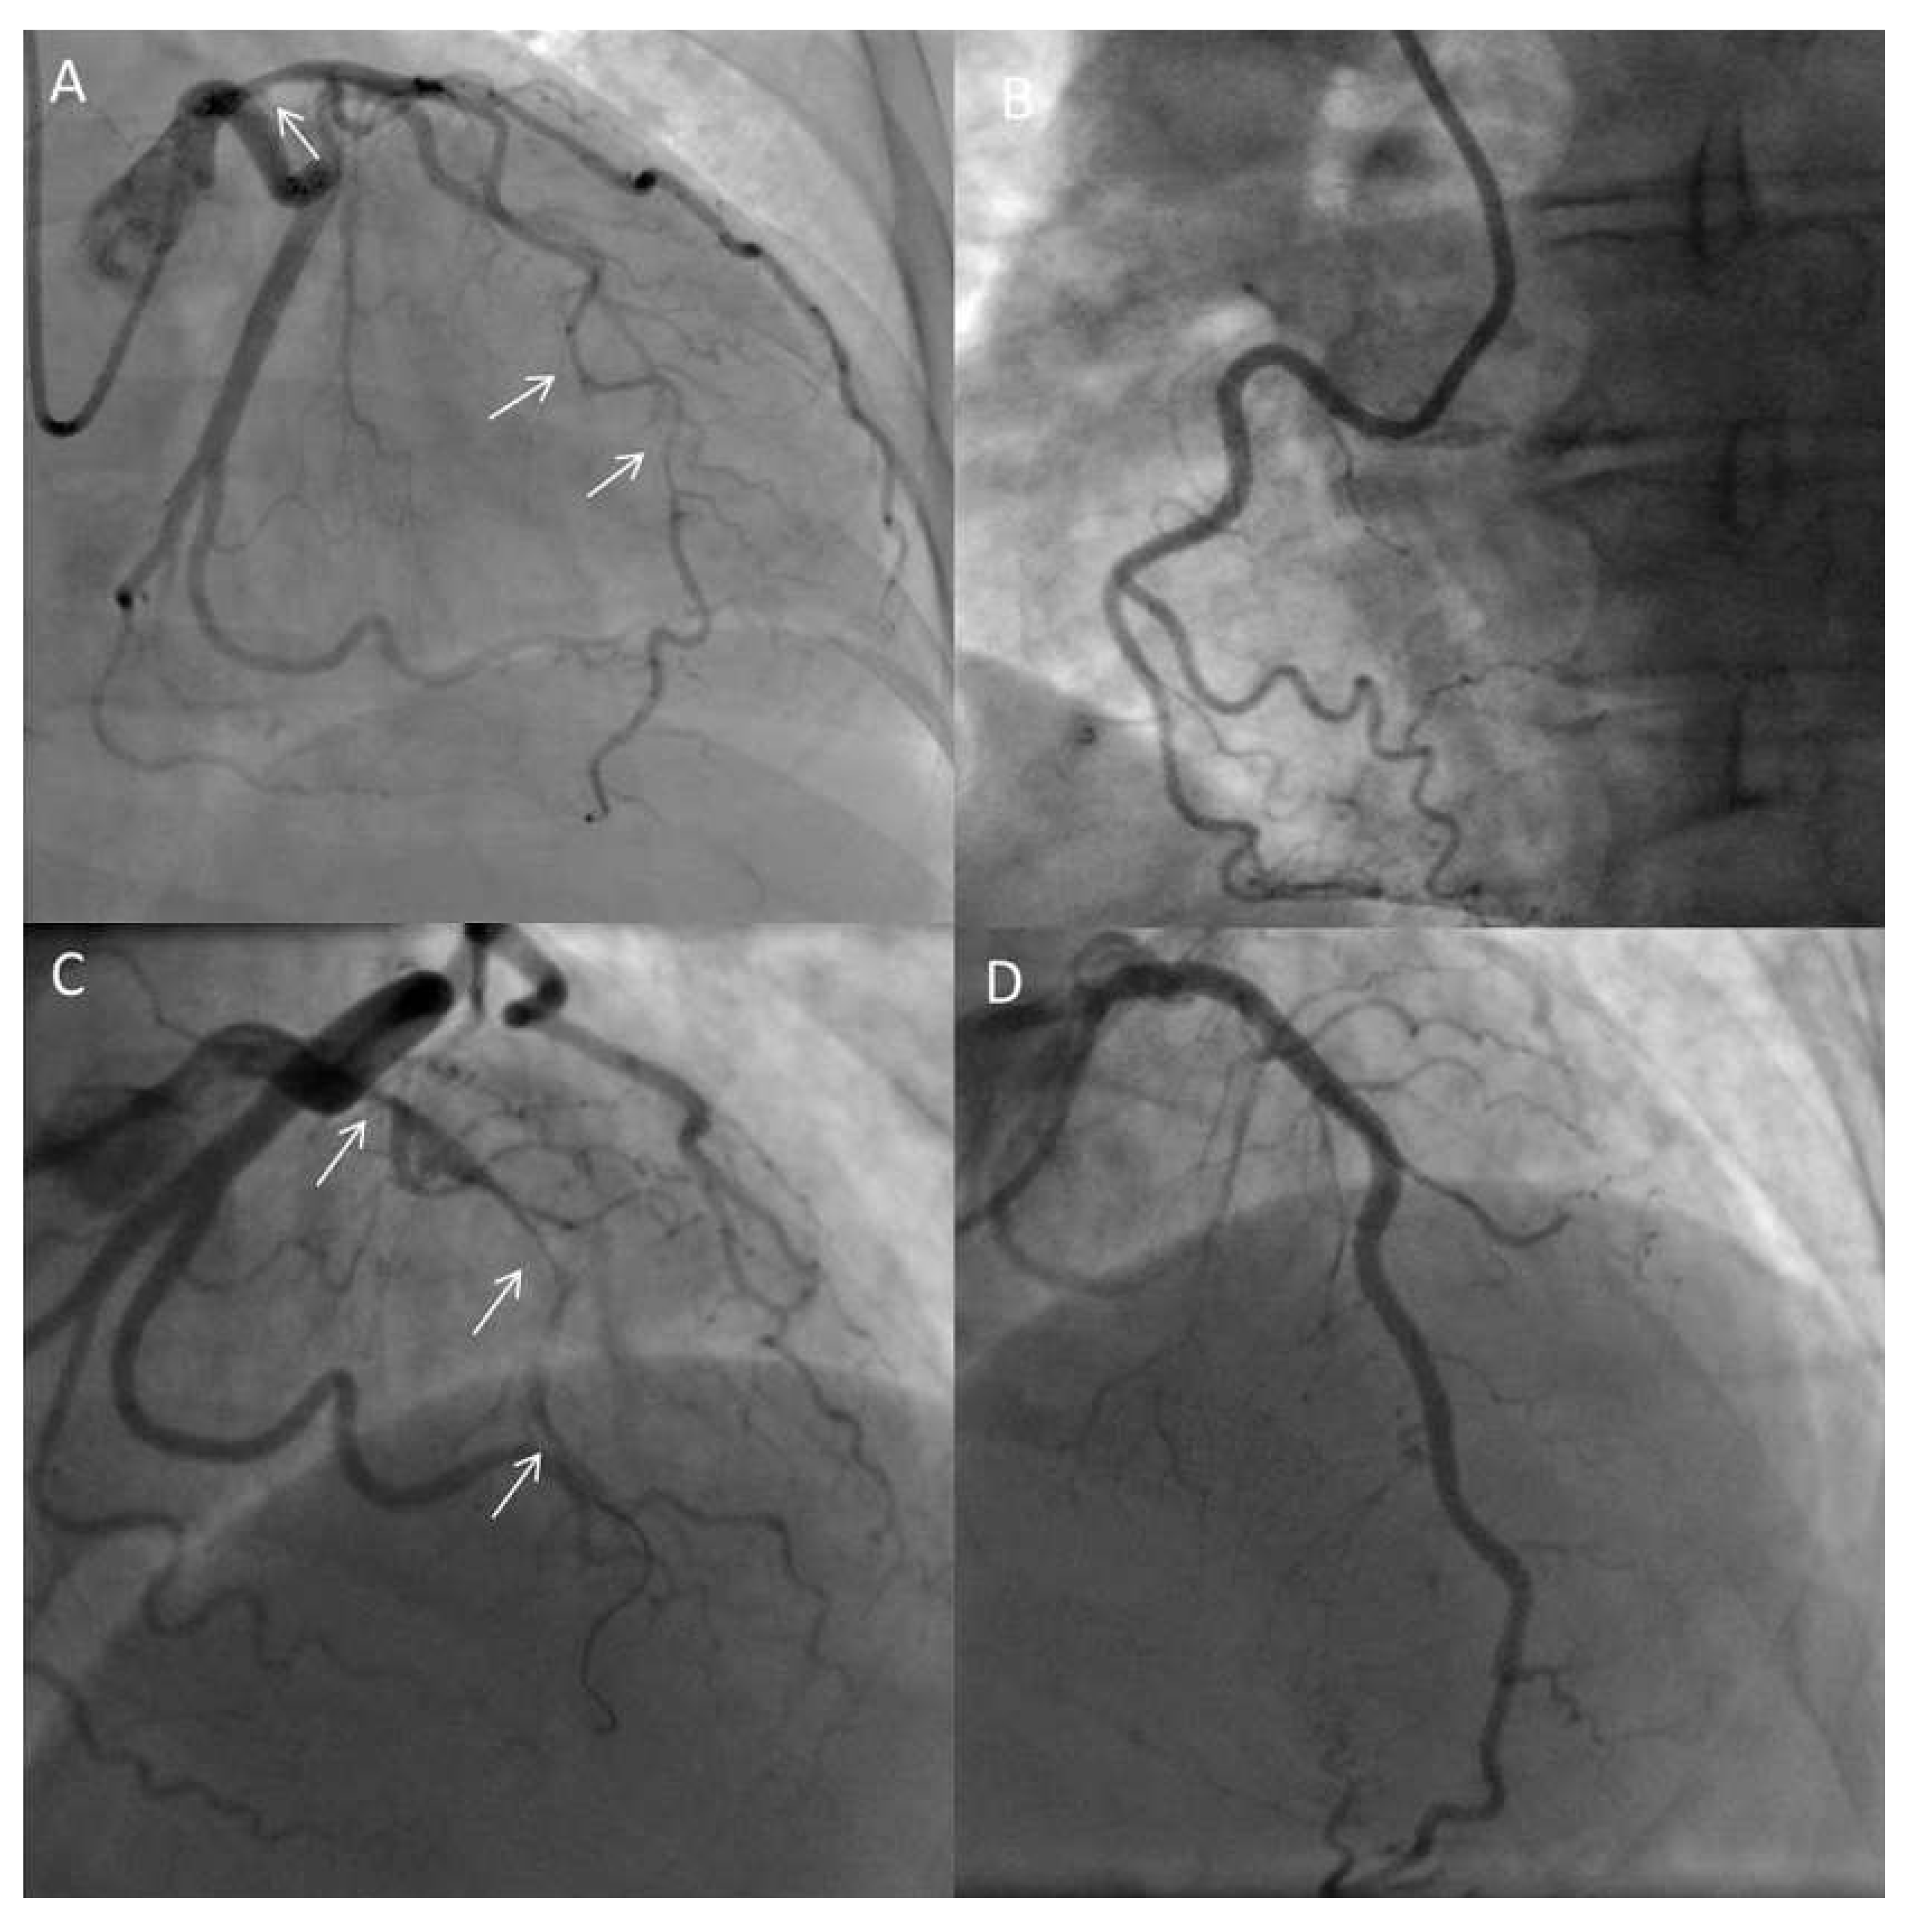

Case Description

Coronary FMD

Spontaneous coronary artery dissection as the complication of coronary FMD

Diagnosis